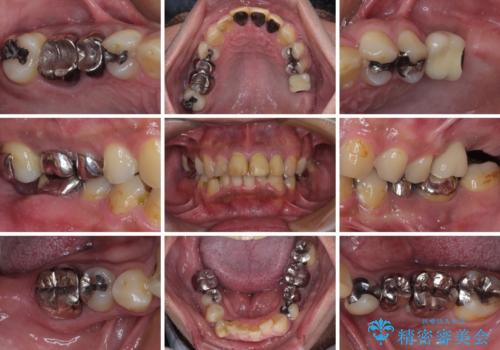

- 黄ばんだ前歯や目立つ奥歯の銀歯をきれいにしたいとのことで来院された患者様です。

欠損している歯や、割れてしまって抜歯の必要な歯などがあり、咬合力が強いため欠損部はインプラント補綴を前提に治療を行うこととしました。

しかしながら、左下の抜歯部位は骨欠損が著しく大きく、多大な垂直的骨造成を要するため、3歯を支台としたブリッジによる補綴治療とし、右下のみをインプラント補綴としました。

小さい修復物の銀歯が装着されている歯はセラミックインレーにて、その他はオールセラミッククラウンにて補綴治療を進めることとしました。

矯正治療にも最初は興味を持たれていましたが、抜歯矯正の可能性が高いことや、治療期間、後戻り防止のためのマウスピース使用などが煩わしいと感じ、補綴治療のみを行うこととなりました。